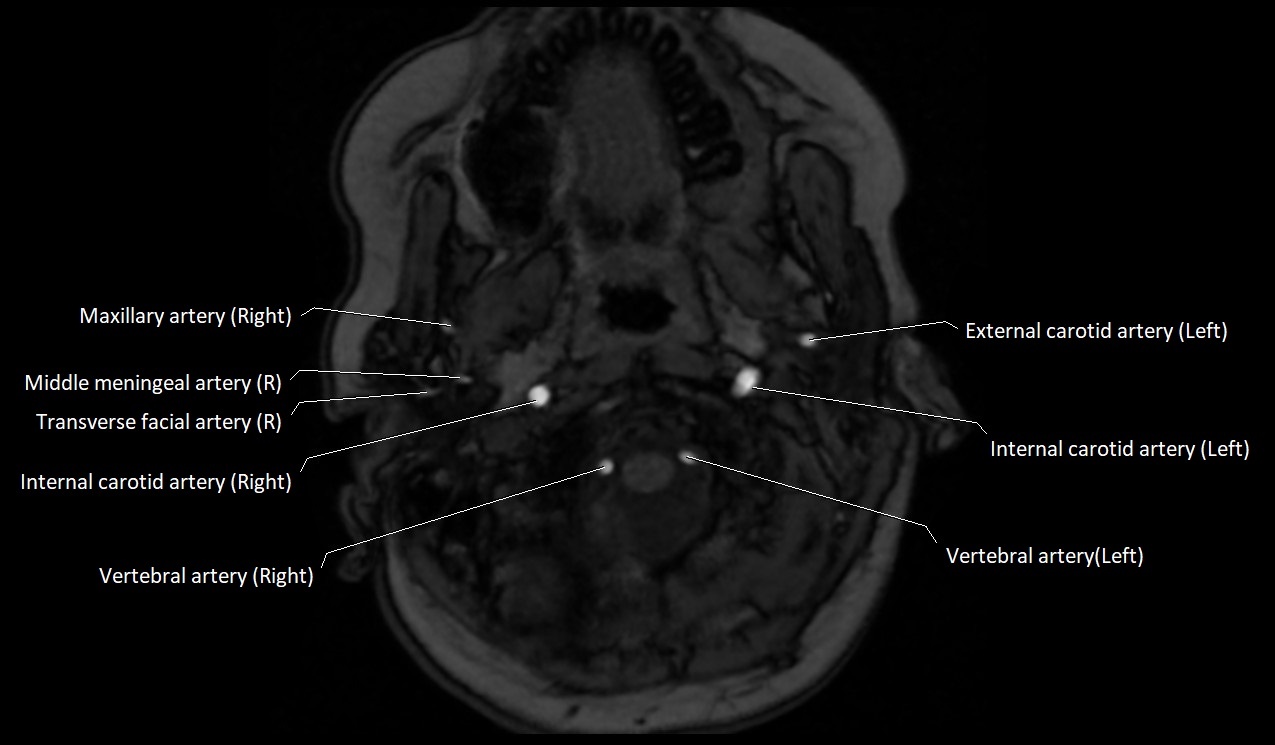

MRI Appearance:

• T1-Weighted Images:

• Appears as a tubular, hypointense (dark) structure relative to muscle

• May show flow void if the blood flow is fast

• T2-Weighted Images:

• Typically hypointense or isointense to muscle, but can be hyperintense if slow flow or stasis is present

MRI images

image